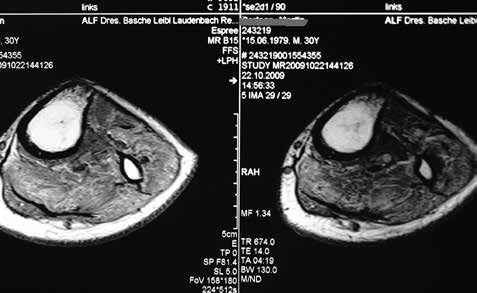

Die Bedeutung der Muskulatur

Mit der Amputation kommt es zum Verlust der Agonisten-Antagonisten-Wirkung. Die Folge ist Atrophie und zunehmender Verlust der Durchblutung bei fettiger Degeneration. Bei der chronisch arteriellen Verschlusskrankheit entstehen allerdings schon präoperativ eine Muskelfaseratrophie und eine Rarefizierung der kontraktilen Elemente in der Muskulatur. Sie sind Ausdruck einer bereits vorher bestehenden Immobilität.

Besonders beim neuropathischen Fuß-Syndrom mit gestörter nervaler Ansteuerung verändert sich auch die physiologische Faserverteilung. Das heißt, die normale Muskelfaserverteilung und die Muskelfaserfläche unterliegen Veränderungen, die u. a. in einem Zusammenhang mit der Wundheilung 16 stehen. Es handelt sich am Unterschenkel um tonische (Halte-)Muskeln (M. gastrocnemius, M. soleus) mit vorwiegend oxidativer Ausstattung bzw. um schnell kontrahierende phasische Muskeln (M. tibialis anterior, Mm. peronaei) mit glykolytisch/oxidativer Ausstattung, wobei gerade die phasische Muskulatur zuerst der Nekrose unterworfen ist und so zu Wundheilungsstörungen vorwiegend lateral im Bereich des M. tibialis anterior führen kann.

Um hier das richtige Maß zu finden, bedarf es einer gewissen Erfahrung. Am besten geeignet ist dafür der dorsale Haut-Muskel-Lappen. Die physiologische Dehnung der Muskelfaser wird über das Zytoskelett am Zellkern wirksam. Mikromechanische Veränderungen am DNS-System bedingen eine Aktivierung der zellulären Syntheseprozesse. Der intraoperative Umgang mit der Muskulatur unterliegt bei allen Autoren außer bei 17 der subjektiven Beurteilung der Muskulatur. Wie unterschiedlich und schwierig das sein kann, gibt Abbildung 14 wieder. Mit der physiologischen Vorspannung gilt es eine physiologische Belastung der Restmuskulatur zu erreichen, um das Verhältnis zwischen pathologisch bzw. physiologisch angesteuerten Hirnarealen zugunsten der Letzteren zu beeinflussen.